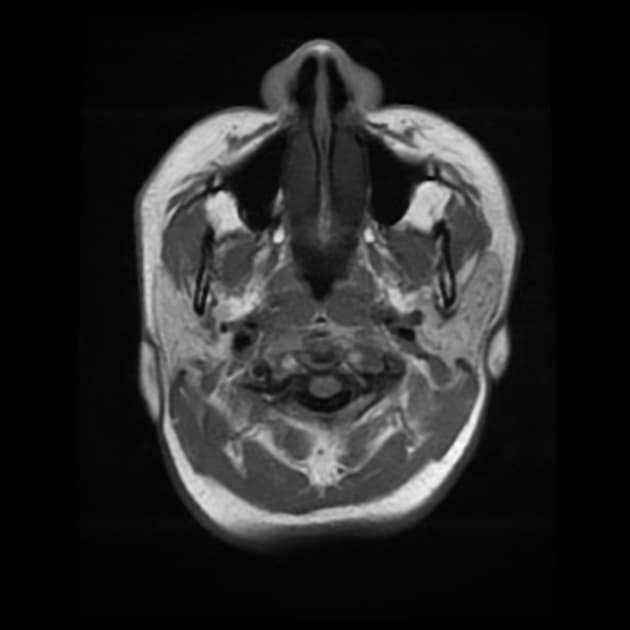

- Khối liên tục với cuống yên, làm giãn cuống này cả phía trên và phía dưới.

- Phù hợp với kiểu tăng quang đặc trưng và nằm trong cuống yên (infundibulum).

- Khối phù hợp với kiểu tăng quang đặc trưng và nằm trong cuống yên (infundibulum).

- Khối liên tục với cuống yên, làm giãn cuống cả phía trên và phía dưới.

- "Đặc điểm hình ảnh gồm khối u ranh giới rõ, tăng quang mạnh, liên tục với và làm giãn cuống yên."

U Pituicytoma là một loại khối u thần kinh đệm lành tính, phát triển chậm và hiếm gặp, xuất phát từ các tế bào pituicyte ở thùy sau tuyến yên hoặc cuống yên. Khối u thường biểu hiện như một tổn thương ranh giới rõ, tăng quang mạnh và liên tục với, đồng thời làm giãn cuống yên. Trên cộng hưởng từ (MRI), khối u thường có tín hiệu đẳng trên hình ảnh T1 và tăng quang đồng nhất sau khi tiêm thuốc cản quang. Việc không có dấu hiệu ác tính, không bệnh toàn thân và tổn thương ổn định dài hạn trên hình ảnh học làm tăng khả năng chẩn đoán u Pituicytoma, ngay cả khi chưa xác định bằng mô bệnh học. Các chẩn đoán phân biệt bao gồm u tuyến yên có liên quan đến cuống yên, u màng não và bệnh tổ chức bào Langerhans, những bệnh này có thể có hình ảnh tương tự. Tuy nhiên, vị trí đặc hiệu trong cuống yên và sự liên tục với cuống làm nghiêng về chẩn đoán u Pituicytoma. Điều trị thường mang tính theo dõi bảo tồn, đặc biệt ở bệnh nhân không có triệu chứng.